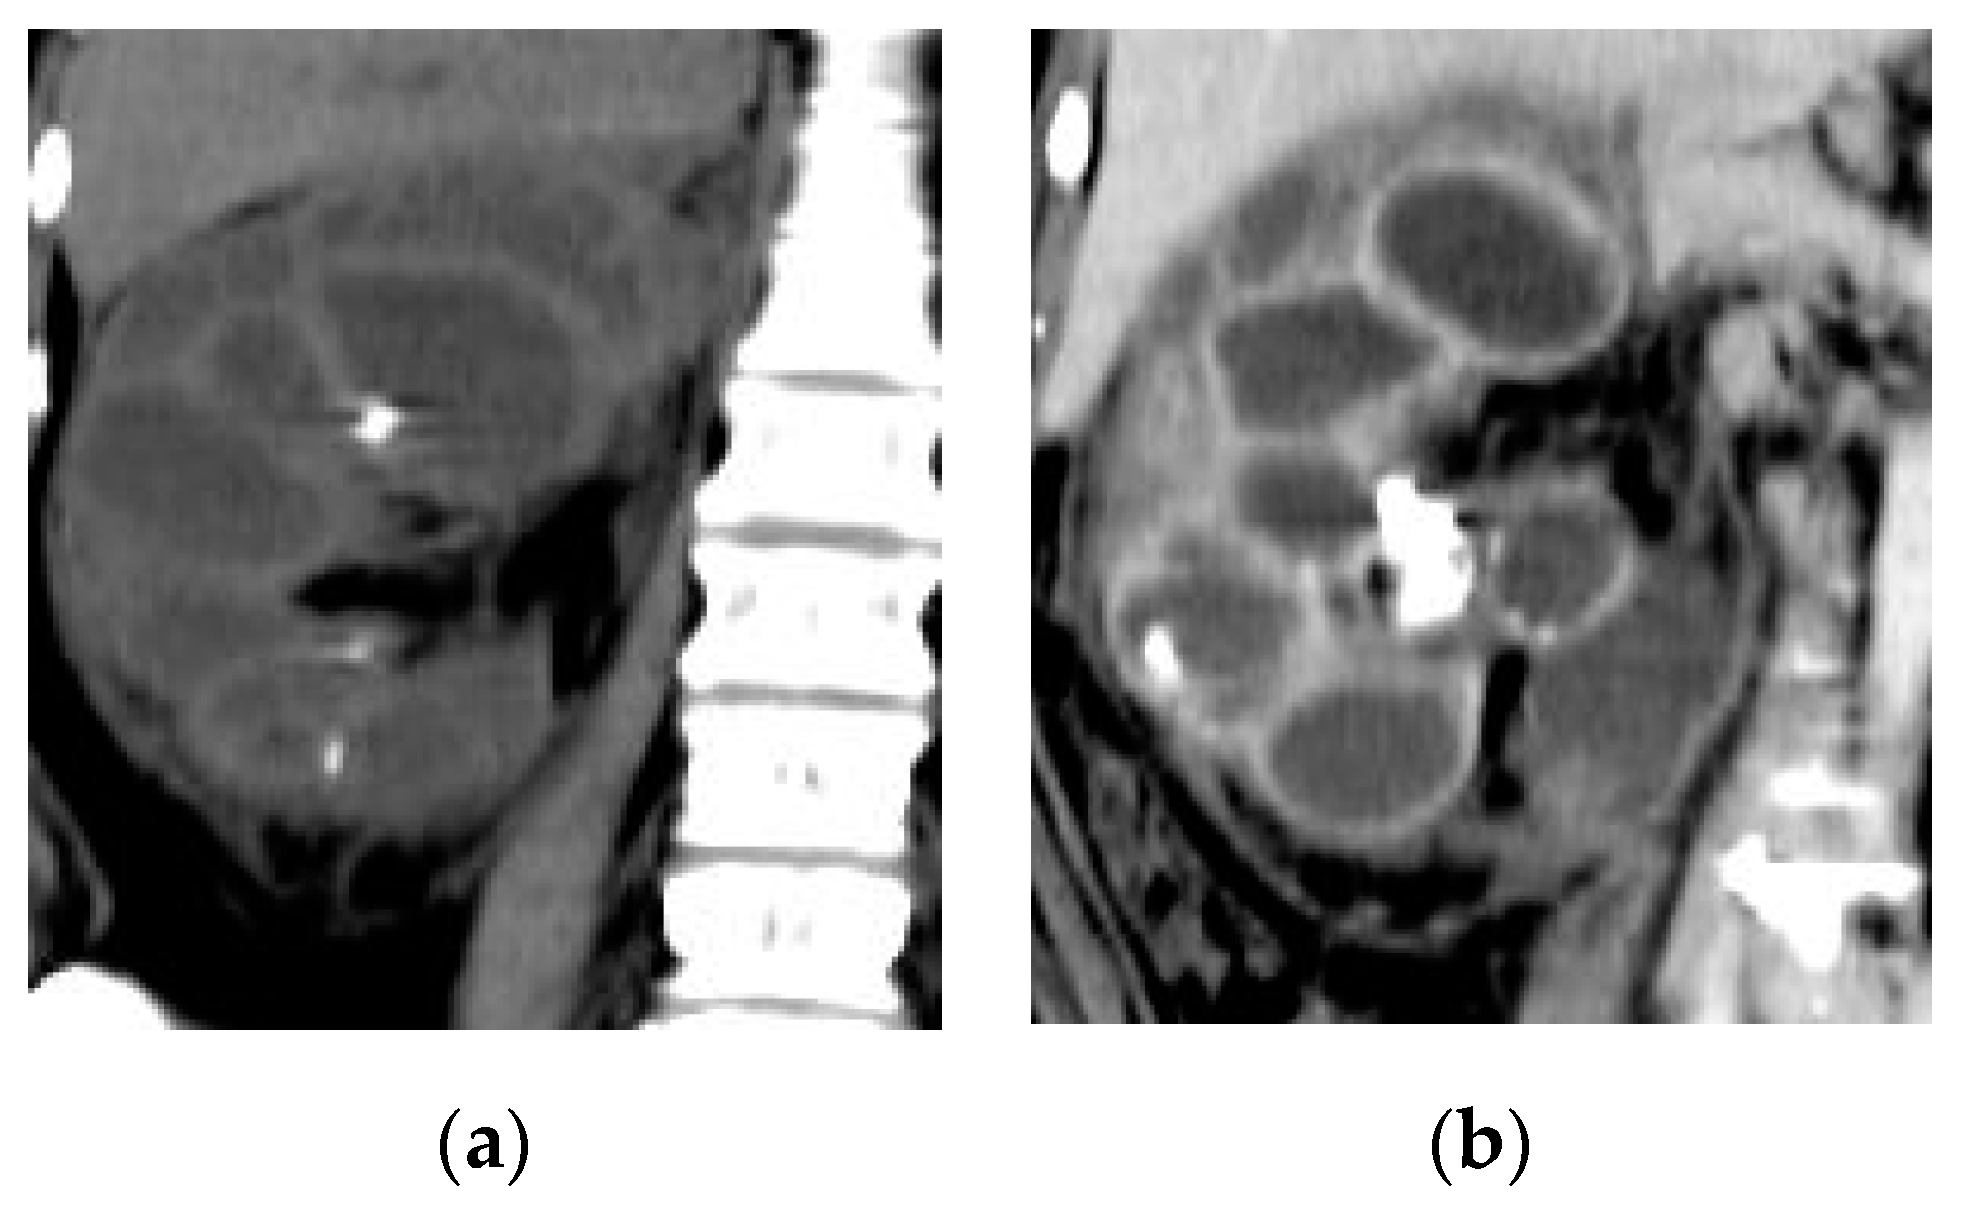

2.7. Urinary Tuberculosis

| Urinary tuberculosis | Calyx stem stenosis with proximal ball-shaped hydrocalyx, cavity communicating with a deformed calyx, putty kidney, ureteric strictures and shortening with beaded appearance, thick-walled contracted bladder. |